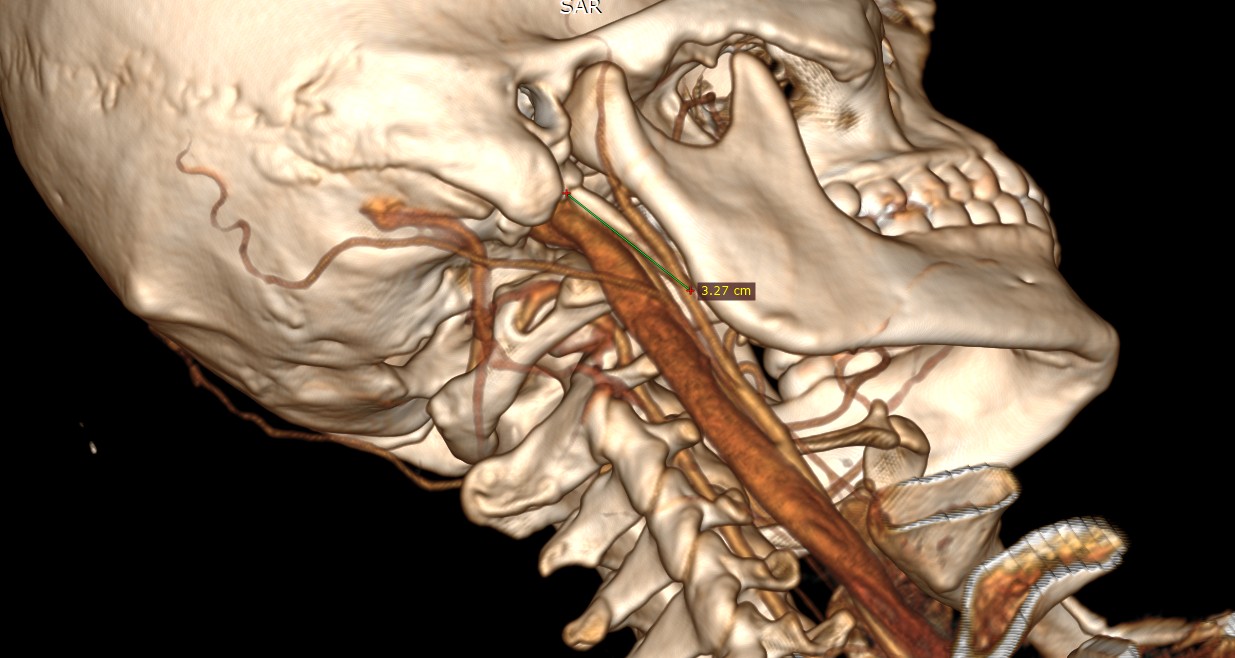

I think I found what’s causing your symptoms. Your right styloid is elongated. I’m getting around 3.3 cm. Your right styloid is quite thick but is shorter and doesn’t seem to be interfering with anything.

Your right IJV is getting compressed between your right styloid and C1. This is important not only because of reduced blood flow out of the brain, but also because the vagus nerve runs between the IJV and C1, so if the IJV is compressed than the vagus is compressed and can cause heart rate and blood pressure changes which can cause dizziness. The reduced flow from IJV compression can also cause dizziness and headaches, brainfog things like that.

Your right styloid tip is in contact with your right ECA, which is the artery that supplies your ear with blood, so any pressure changes from your styloid hitting that artery or compressing it, would likely cause pressure changes to your ear which can cause a bunch of ear symptoms (fullness, ringing/tinnitus) and possibly dizziness since the ears are important in the vestibular system.

what you and I have in common is the ECA involvement from our styloids. Since we both are dizzy and it gets worse in the dark, I really now think that ECA compression is the culprit for that specific symptom. It’s the only thing besides the IJV that you and I have in common in our scans. Here’s my styloids hitting my ECAs. Any head movements theoretically would change the pressure gradients in our ECAs due to our styloids moving with our heads.